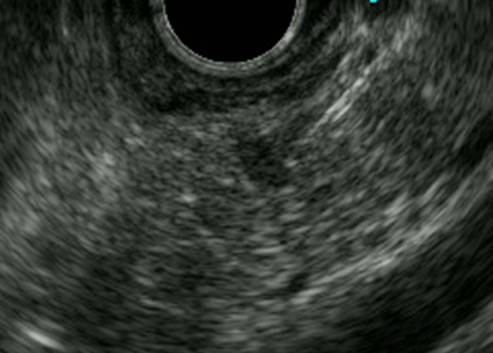

超音波内視鏡(EUS):

大きさ10mmの低エコー腫瘍(黄色矢印)をはっきりと認識できます。

超音波内視鏡下穿刺吸引法(EUS-FNA)で膵癌と診断できました。

【病理診断】大きさ15mmの浸潤性膵管癌でした。

膵頭十二指腸切除を施行し完全に切除ができました。pT1cN0M0 pStageIAでした。